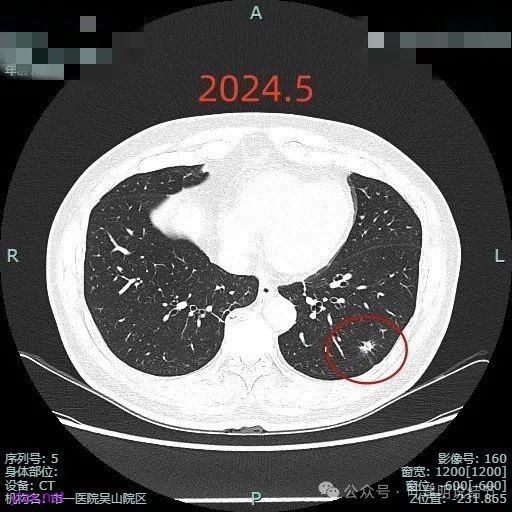

我们把三次薄层的放在一起看看:

感悟:

这个结节虽然仍在,或许也有人觉得密度减低也不是太明显,但我想至少随访长达1年是没有明显进展的,而且虽有毛刺但显得过长;虽有空泡但显得更像细支气管扩张;虽有灶内密度杂乱但更显得像慢性炎的杂乱;虽有血管进入但显得异常增粗是不明显的;虽表面不平但整体缺乏收缩力,也无膨胀感。所以总体上更符合慢性炎些,至少是能随访的。此例之所以当时就觉得像炎性些,最关键的也不是上面讲的这几点,而是横断面看圆形或类圆形且有相应恶性影像特征,但纵向是偏长条的,再加上上述影像特征有却不是典型恶性的毛刺、空泡与血管征等,所以才倾向炎性的考虑。我想最终的结果仍是要病理依据,但我们从风险高低以及前后对比综合评估应该是不变的原则与最接近真相的。